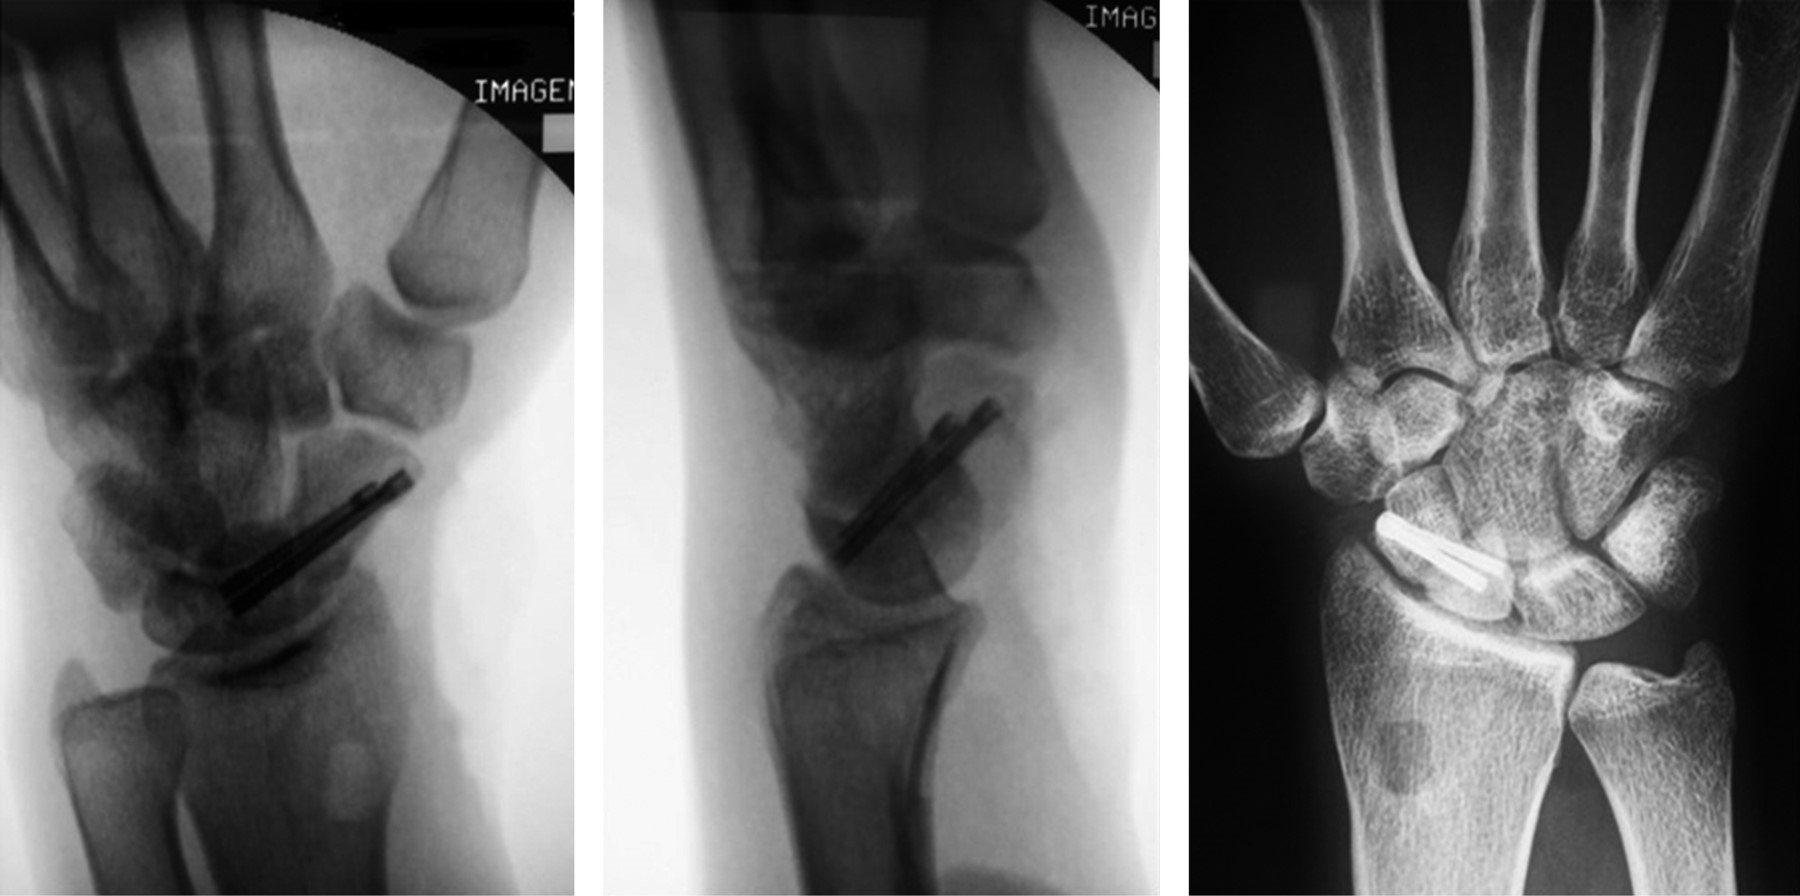

Todas las fracturas se encontraron en la cintura del escafoides y fueron catalogadas mediante la clasificación de Herbert y Fisher propuesta en 19846 utilizando radiografías anteroposterior, lateral y oblicua de muñeca (Figura 1). Una de las fracturas se clasificó como seudoartrosis (tipo D2) y las tres restantes como no unión fibrosa (tipo D1). Tres presentaron inestabilidad dorsal del segmento intercalado y dos deformidad en joroba del escafoides.

Figura 1